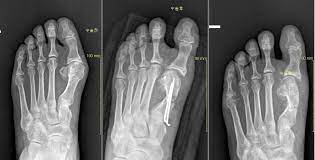

무지외반증은 엄지 발가락이 검지발가락 쪽으로 휘어지면서 엄지발가락 바깥쪽 끝 부분이 과하게 튀어나오게 된다. 이 튀어 나오게 된 부분이 신발 등에 자극을 지속적으로 받으면서 통증이 생기고 염증이 일어나게 되는데 심하면 엄지발이 휘어지면서 검지발가락과 다른 발가락에도 변형을 주거나 압박을 주어 피부 궤양이 발생하거나 탈구, 변형 등이 생기기도 한다.

무지외반증은 엄지발가락이 휜 정도만 보아도 진단이 가능한데, 발가락이 휜 정도 검지와 엄지가 겹치는 정도, 다른 발가락들의 통증 여부 굳은살 정도에 따라 병의 정도를 진단하며 치료를 진행 합니다. 다행히 저의 경우는 아주 심한 정도는 아니었어서 (인터넷상으로 확인해 보니 2 단계 정도였다고 판단됨) 수술을 고려하지는 않았는데요 심한 경우는 수술이 필요할 수도 있으니 꼭 전문의와 상담하시길 권해 드립니다.